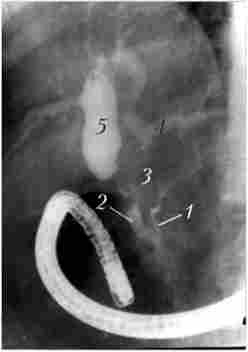

рентгенологічні дослідження. Рентгенологічне контрастне дослідження дванадцятипалої кишки дозволяє виявити патологічний процес, що розташовується не тільки в самій кишці, але і в органах, безпосередньо прилеглих до неї. Застосування релаксационной дуоде- монографій дозволяє, як правило, виявити пухлину БДС і, в деяких випадках, за непрямими ознаками - головки підшлункової залози, а також судити про стан стінок самої дванадцятипалої кишки (рис. 21.8 і 21.9). Деформація контурів, звуження просвіту ДПК, розгорнення її петлі служать непрямими ознаками, що дозволяє висловити припущення про наявність патологічних змін в ПЖ тільки в тому випадку, якщо пухлина досягне значної величини. При РПЖ відхилення від норми виявляють лише у 50% хворих.

Дуоденографія в умовах гіпотонії

Мал. 21.8. Дуоденографія в умовах гіпотонії:

1 - ділянку відсутності рельєфу слизової оболонки протягом 2 см по медіального контуру дванадцятипалої кишки у верхній половині спадної частини кишки; 2 - порожнину розпалася пухлини за межами кишки,

в яку затікає контраст

Макропрепарат після панкреатодуоденальной резекції, виконаної тієї ж хворий, знімок якої показаний на рис. 21.8

Мал. 21.9. Макропрепарат після панкреатодуоденальной резекції, виконаної тієї ж хворий, знімок якої показаний на рис. 21.8: